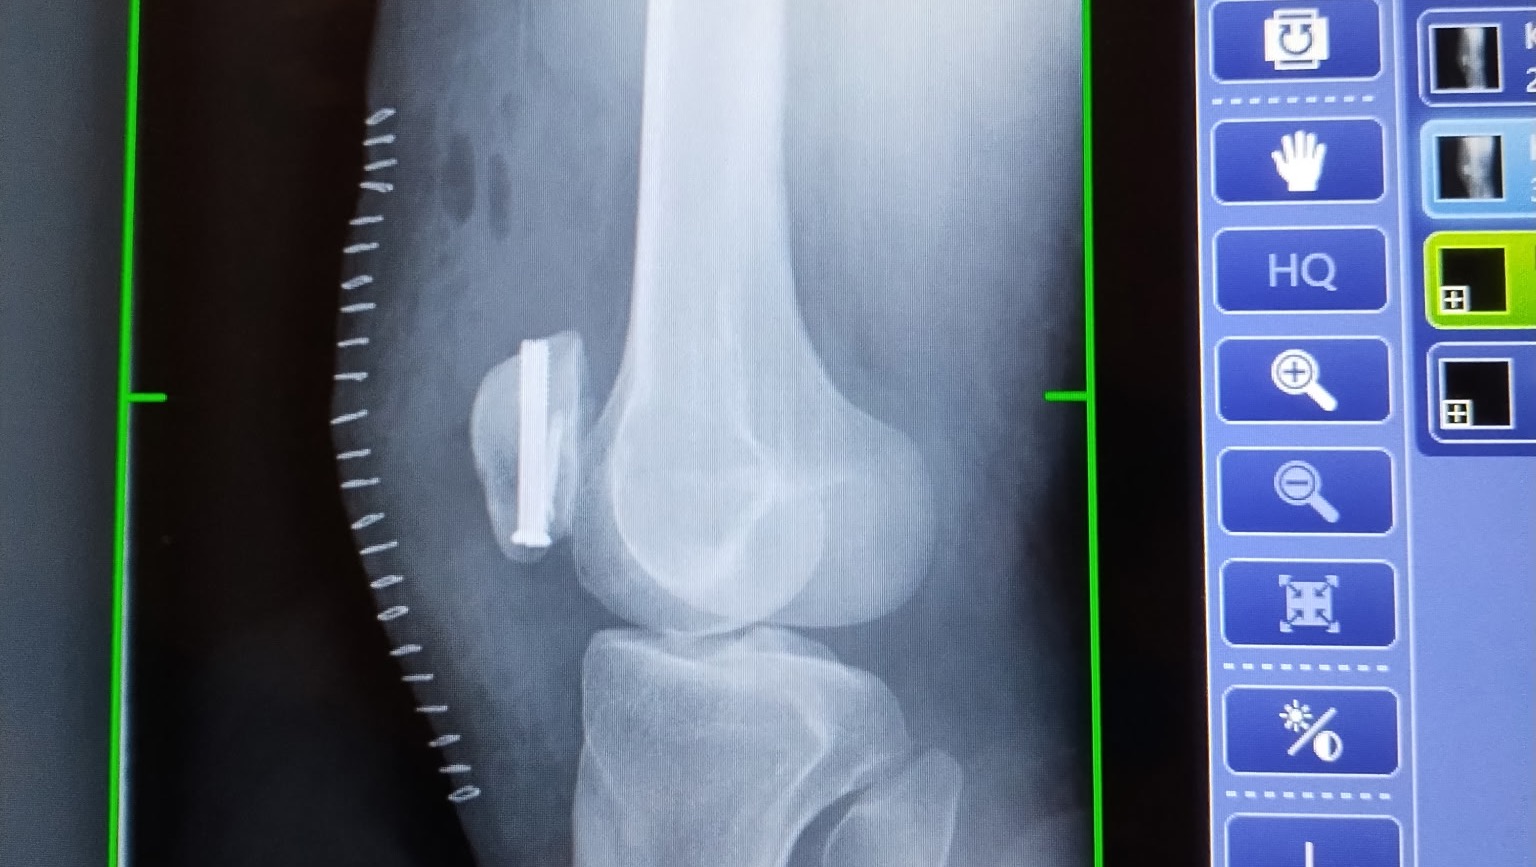

I have already had knee repair surgery, in which I got 4 screws to hold it together and 23 staples to seal the surgical site. I am on the long road to recovery. Due to this injury, I am not currently allowed to work. With winter coming I am in need of assistance with covering my monthly costs while I recover. Over the next several months, I will need to learn to walk again.